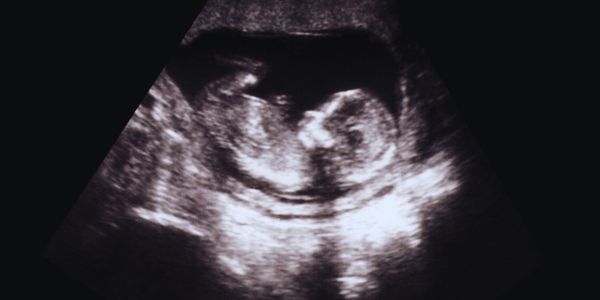

Bem-vindo ao Pais de Dois Heróis! De fato, a jornada inicial de Lucas começou em 2013, numa consulta que partiu meu coração. O ultrassom mostrou um aumento na bexiga de Lucas, ainda nas oito semanas, deste modo, lágrimas escorreram dos olhos de Paula. Meu peito apertou. Mas uma voz interna gritou esperança. Conhecido como “leãozinho de cristal”, sua jornada inicial, Lucas trouxe luz à escuridão. Por isso, esta história, cheia de amor e luta, toca pais que enfrentam o mesmo medo.

Além disso, aquele dia na clínica ficou gravado em mim. O ginecologista apontou uma anormalidade, pediu um novo exame, assim, meu mundo parou. Vi o pavor nos olhos de Paula. Segurei sua mão trêmula, prometendo nunca desistir. Essa foi a jornada inicial de Lucas. Também, médicos sugeriram aborto por causa da lei em que crianças com alguma síndrome, os pais tem direito ao aborto. Mas nossos corações disseram não. Como fazer: Guarde cada detalhe. Apoie seu parceiro. Busque força.

Por outro lado, no dia seguinte, um colega chamado pelo ginecologista experiente, confirmou o pior. A bexiga de Lucas estava aumentada. Assim que ouvi, essa informação, senti um nó na garganta. Fomos encaminhados à Unicamp, onde o Dr. Fábio Peralta nos acolheu. Do mesmo modo, sua voz calma acalmou meu choro. Essa foi a jornada inicial de Lucas. Pressões por aborto voltaram. Olhei para Paula e sussurrei: “Ele merece viver.” Como fazer: Confie nos médicos. Segure a mão de quem ama.